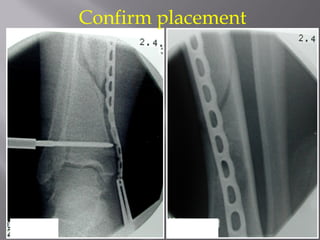

Confirm placement

Pre-size and bendplate Or use precountoured plate